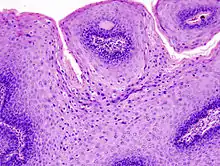

The diagnosis of genital warts is most often made visually, but may require confirmation by biopsy in some cases.[20] Smaller warts may occasionally be confused with molluscum contagiosum.[19] Genital warts, histopathologically, characteristically rise above the skin surface due to enlargement of the dermal papillae, have parakeratosis and the characteristic nuclear changes typical of HPV infections (nuclear enlargement with perinuclear clearing). DNA tests are available for diagnosis of high-risk HPV infections. Because genital warts are caused by low-risk HPV types, DNA tests cannot be used for diagnosis of genital warts or other low-risk HPV infections.[4]